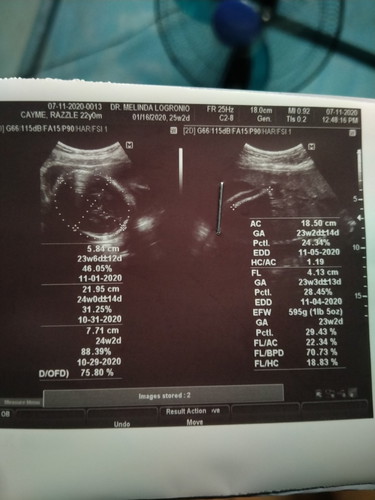

Mga momsh BABAE PO BA O LALAKI ? BASE PO SA ULTRASOUND KO PO ? thanks po

Double check po sis sa COMMENTS dun sa paper mo. Naka cut sya eh, usually nakalagay na rin yan dun kung anong gender.